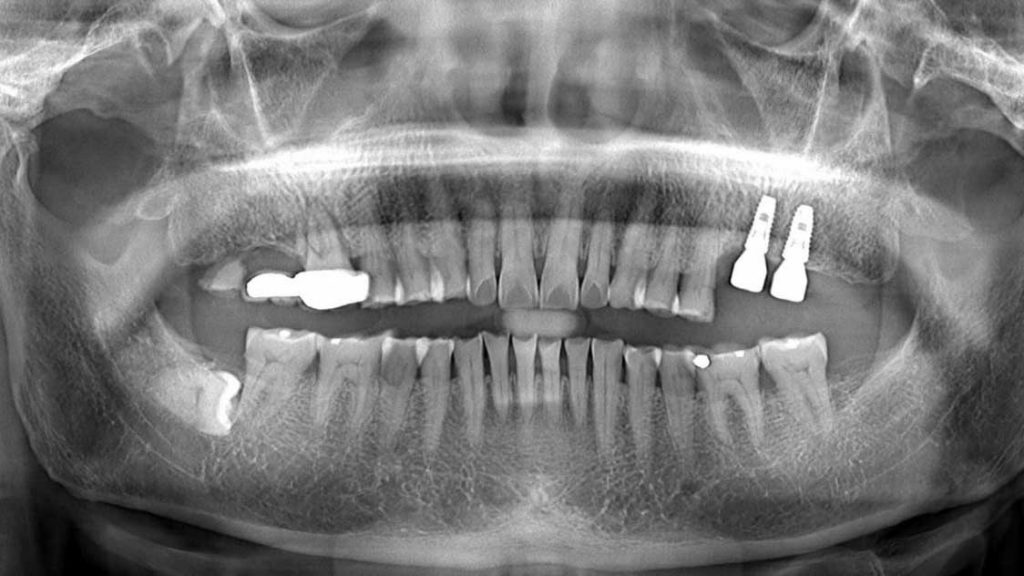

- Chụp CT và khảo sát kết quả thông qua phần mềm thông minh

- Tiến hành cấy ghép một trụ implant titanium vào xương hàm, thông thường gồm 4 trụ (2 trụ phí trước được cấy ghép thẳng và 2 trụ phía sau được cấy ghép nghiêng).